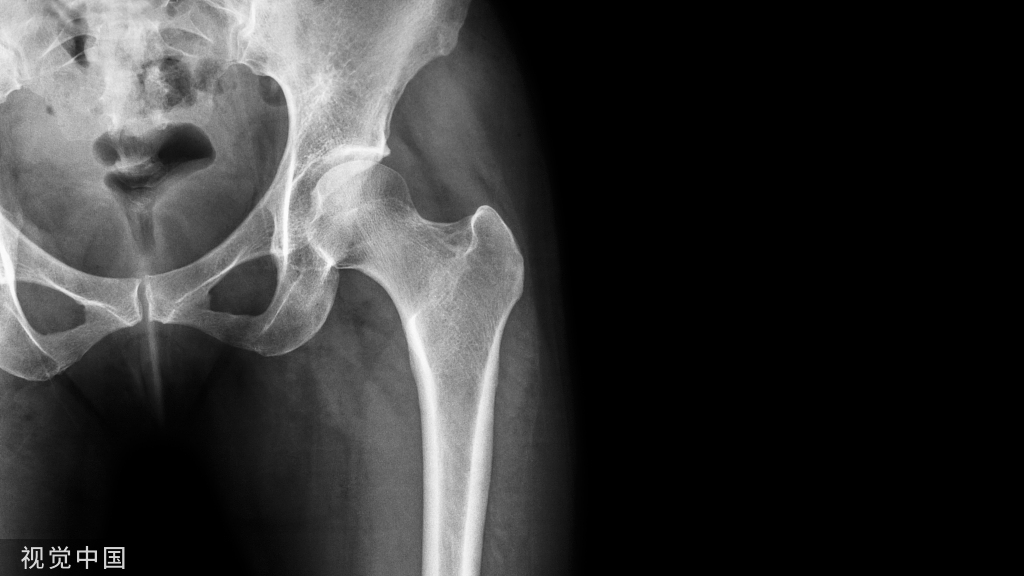

患者髋臼骨量预存较少

对于一些髋臼骨量预存比较少的患者。比如,本身后壁就比较薄,这时如果挫的力道、把持的方向不对或前倾角偏大,就有可能把后壁给挫掉了,夹持不住预期的臼杯。